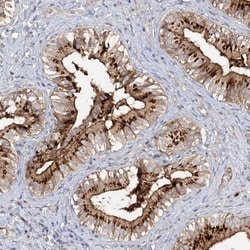

Invitrogen™ FGF19 Polyclonal Antibody

Brand: Invitrogen™ PA5111069

| Immunohistochemistry (Paraffin) | |